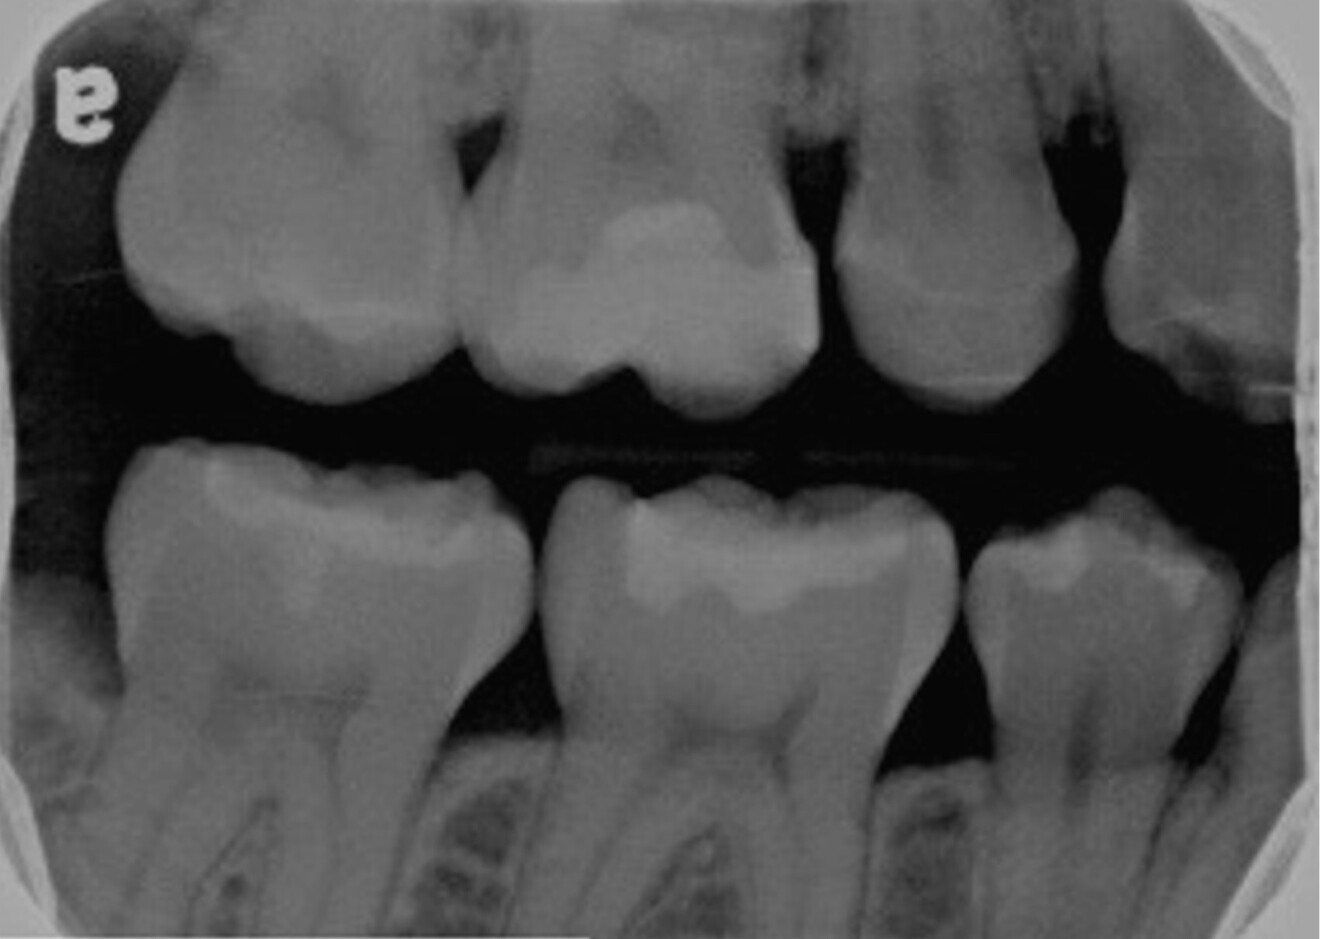

Fig. 2: Bitewing radiograph showing evidence of a deep restoration in tooth #16 at mesial level. Under-mineralised tissue was found close to the mesial pulp horn.